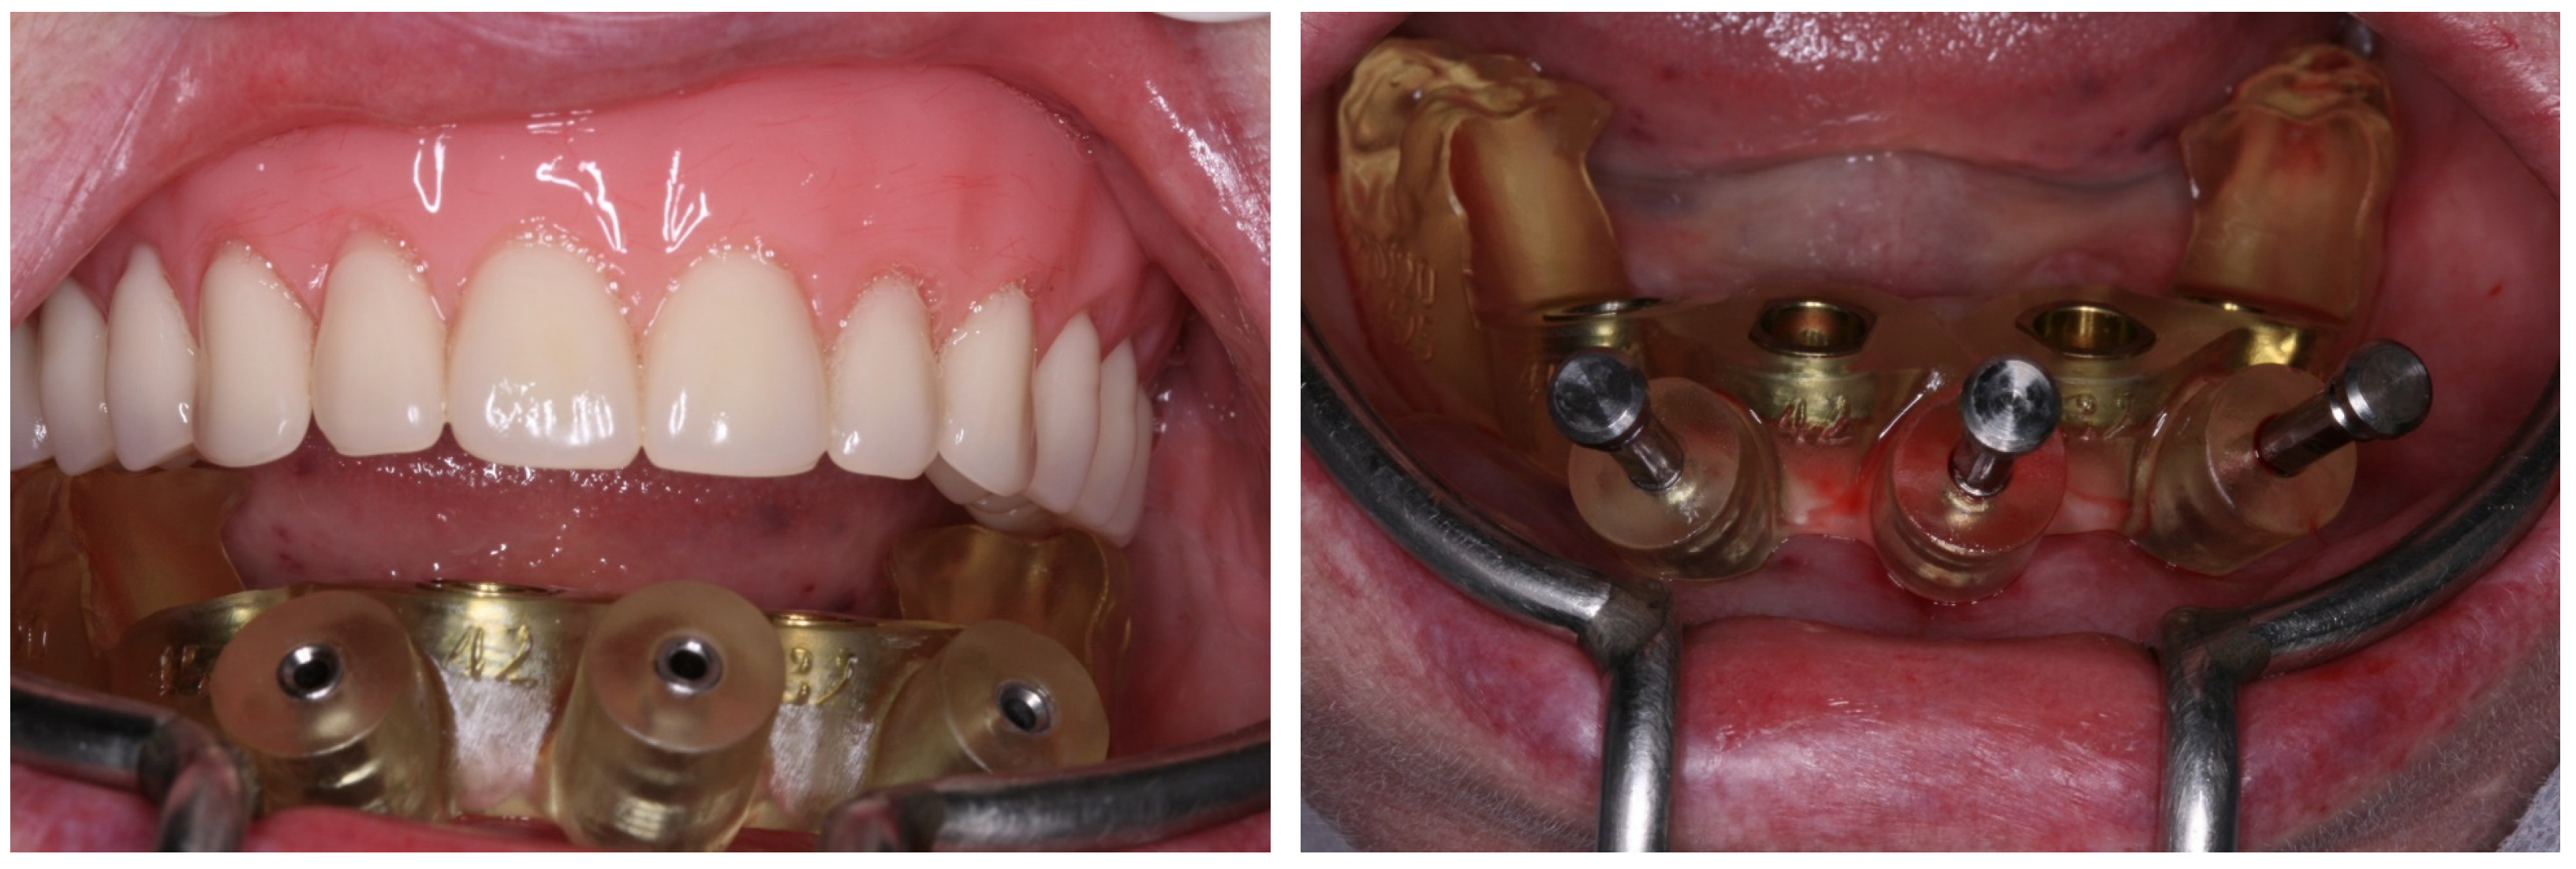

2. Case Report